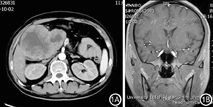

患者男性,27岁。以"体检发现胰腺占位性病变2月"入院。体检:面部色素沉积,皮肤黯黑、皮肤巩膜无黄染。既往无糖尿病史、高血压病史。无外源性激素服用史。全腹CT平扫及增强见胰头部一混合回声病灶,约119 mm×63 mm;双侧肾上腺形态饱满(图1A)。实验室检查:尿游离皮质醇58184.16 nmol/24 h;8点时促肾上腺皮质激素(adreno cortico tropic hormone, ACTH)6.04 pmol/L,16点时5.32 pmol/L,24点时4.26 pmol/L;上午皮质醇>1655.31 nmol/L,下午也>1655.31 nmol/L;胰岛素0分时101.70 pmol/L,60分时372.80 pmol/L,120分是342.50 pmol/L;C-肽0分时1.06 nmol/L,60分时2.01 nmol/L,120分时2.16 nmol/L;促甲状腺0.437 uIU/ml,游离T32.09 pmol/L,游离T48.09 pmol/L。头颅磁共振示鞍内垂体高径约0.5 cm,增强扫描垂体信号均匀,垂体柄居中;视交叉的形态、走形未见异常;双侧海绵窦未见异常信号(图1B)。肺部CT未发现异常。进一步完善肾上腺多排CT扫描示双侧肾上腺增粗,形态欠规则。临床表现为顽固性低钾,给予持续性静脉钾离子泵入。经多学科会诊考虑胰腺神经内分泌肿瘤致异位ACTH综合征。择期行胰十二指肠切除术,术后病理报告:考虑胰腺腺泡细胞癌,伴出血、坏死及囊性变,形态学考虑神经内分泌肿瘤(G3)可能性大。免疫组化染色:CgA(-), Syn(-),Ki67 (+), AACT(+), CK8(+), CK18(+),ACTH(-),CD56(散在+),核分裂象3~6个/10HPF(图2)。胰十二指肠切除术后复查皮质醇指标,皮质醇上午为422.19 nmol/L,下午为987.76 nmol/L,尿24小时皮质醇10889.10 nmol/L,较术前均有下降。术后无出血及胰漏、胆漏等并发症,但出现发热,腹腔感染,肺部感染及一型呼吸衰竭。给予积极抗炎及呼吸机辅助呼吸对症治疗,但由于经济原因患者最终选择出院。